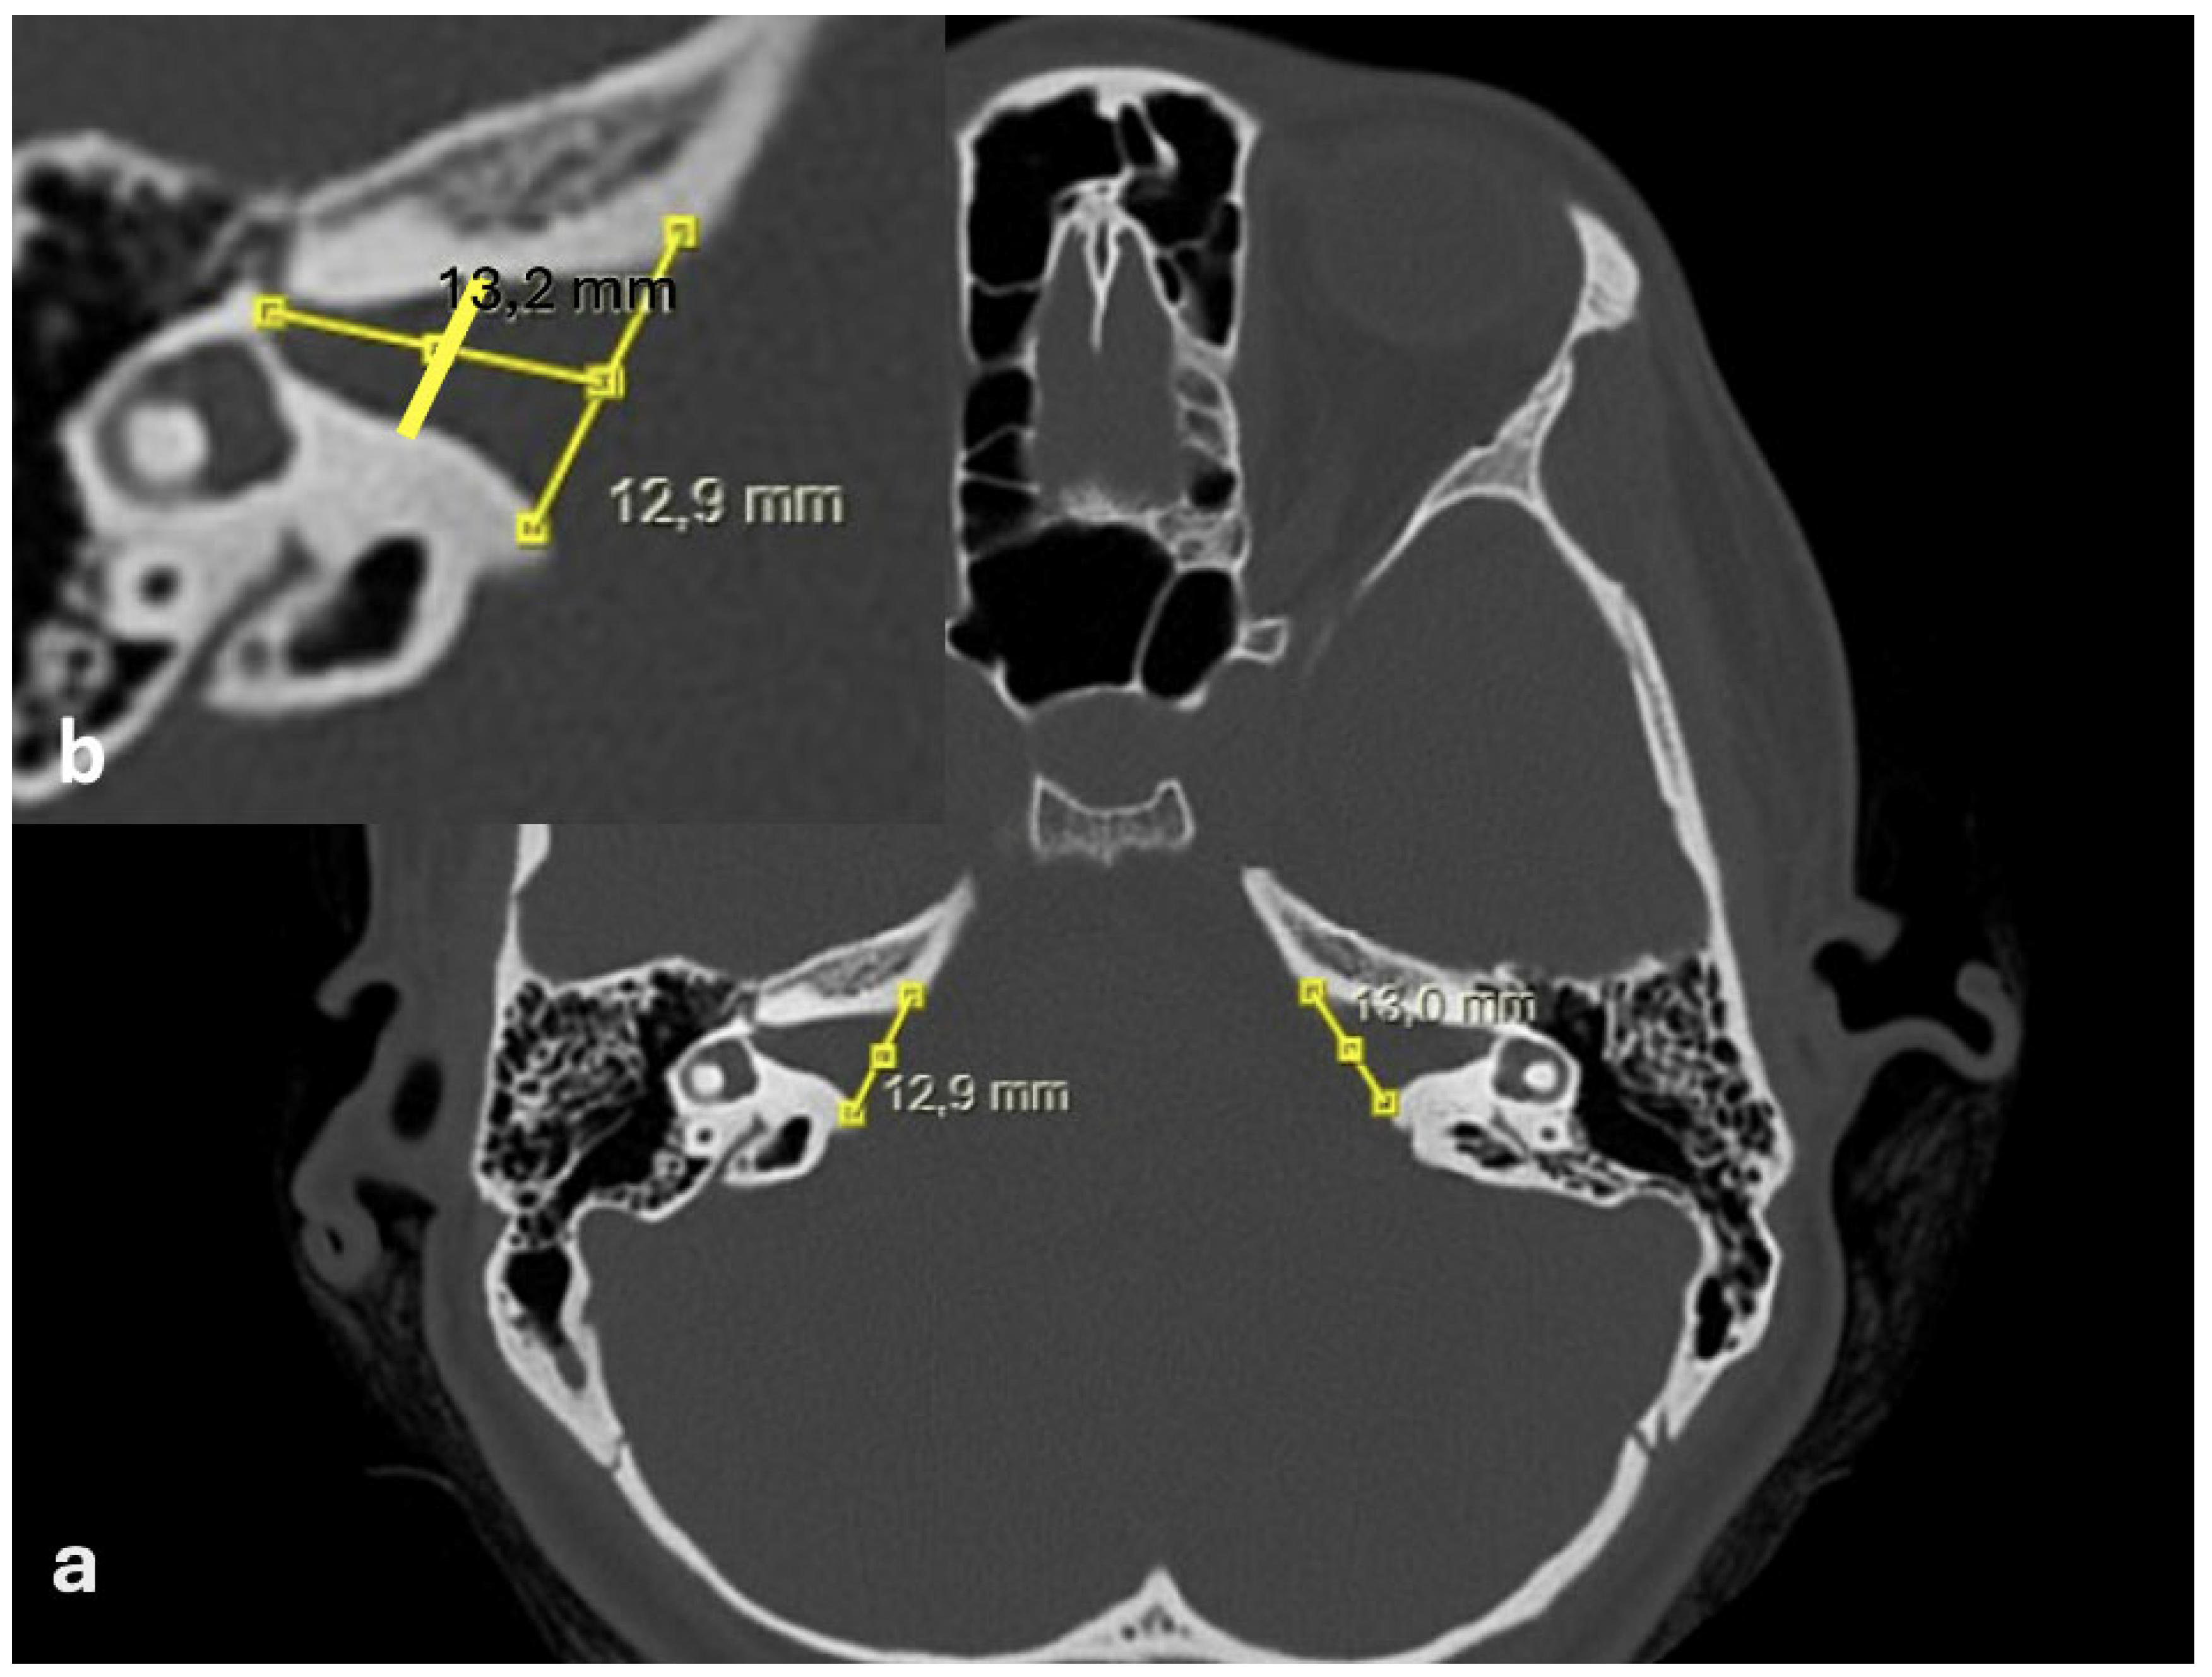

- Bilateral IAM inlet diameter: the distance between the anterior and posterior walls at the most medial part of the IAM (Figure 2);

- Bilateral IAM length: the distance between the most lateral point of the IAM and the midpoint of the inlet diameter (Figure 2);

- Bilateral IAM mid-diameter: the distance measured at the midpoint of the IAM length, parallel to the inlet diameter (Figure 2);